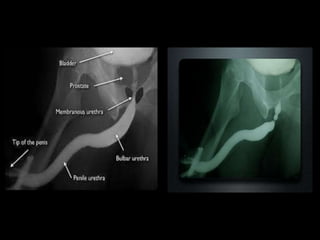

Image interpretation

• Normal retrograde urethrogram (RGU):

• If the radiopaque contrast is injected properly,

the entire anterior and posterior urethra should

be filled with contrast and seen to jet into the

bladder neck. The verumontanum is seen as an

ovoid filling defect in the posterior urethra

• The distal end of the verumontanum marks the

proximal boundary of the membranous urethra

and constitutes the urethra that passes through

the urogenital diaphragm.

Affect of patient positioning on the appearance of the urethra during retrograde

urethrography. (a) Retrograde urethrogram obtained with the patient supine shows

the bulbous urethra as a diverticulum-like outpouching. (b) On a retrograde

urethrogram obtained after the patient was placed in a steep oblique position with

the penis stretched, the penoscrotal junction and bulbous urethra have a normal

appearance.